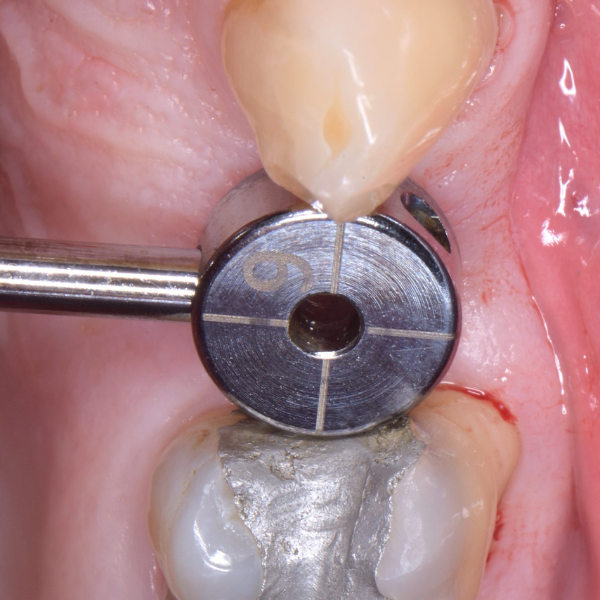

Anterior Implant Placement & Graft